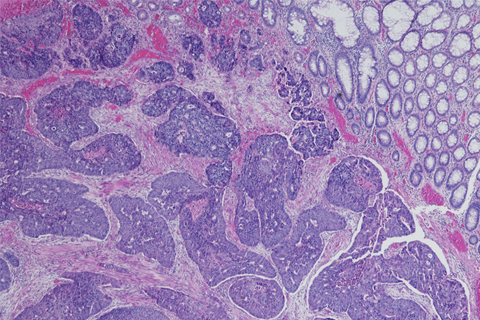

The Furuya Laboratory focuses on two main areas: 1) the role of sphingolipid signaling cascade in cancers, such as colorectal, breast and bladder cancer, 2) urinary biomarkers for early detection, prognostics and prediction of the response to treatment of bladder cancer. The Furuya Laboratory has extensive research experience in animal cancer models including colorectal, bladder, breast and tongue cancers.

- The role of sphingosine kinase 1 expression in abdominal immune cells in colorectal cancer.